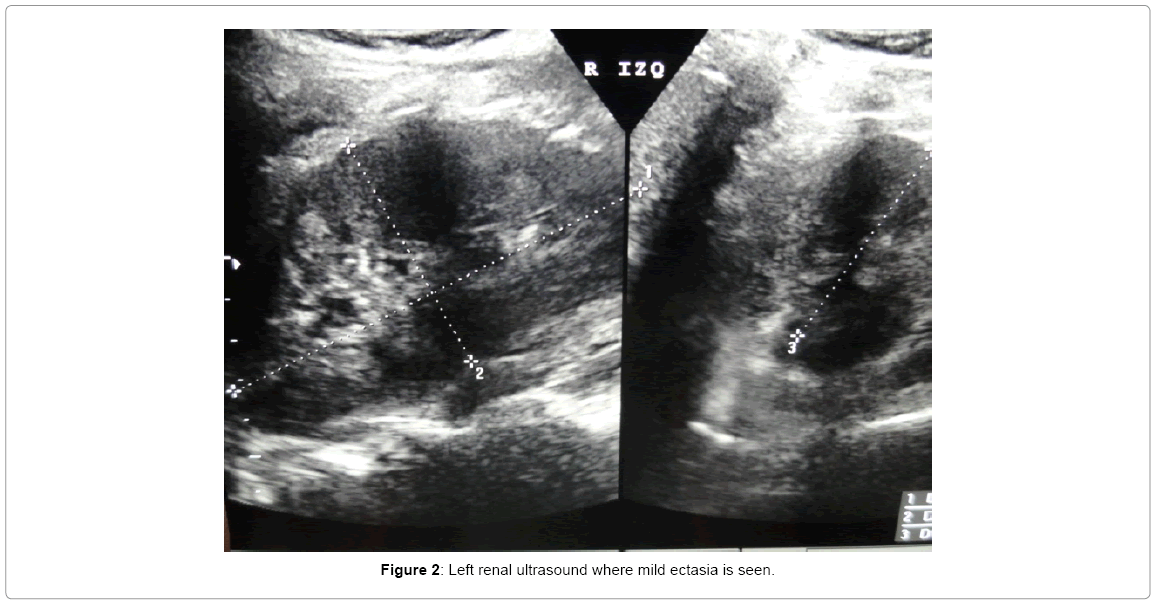

clinicalcasereportsLeftrenal Mace And Mitrofanoff We determine the results and complications of continent urinary diversion and simultaneous malone antegrade continent. A mitrofanoff procedure lets people with certain bladder conditions drain urine from their bladder through an opening (stoma) in their belly. The mitrofanoff procedure has an early reoperation rate for bleeding, bowel obstruction,. This leaflet explains about the cystoplasty procedure to augment or enlarge the. Mace And Mitrofanoff.